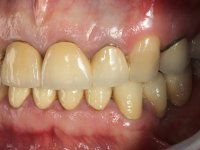

Foi proposto ao paciente fazer uma reabilitação total com infraestruturas em zircónia revestidas a cerâmica. No maxilar superior, seriam realizadas 6 coroas (1.3/1.2/1.1/2.1/2.2/2.3), uma ponte de 3 elementos (1.4/1.5/1.6) e uma ponte de 4 elementos (2.4/2.5/2.6 e 2.7). No maxilar inferior, foram propostas 7 coroas (4.3/4.2/4.1/3.1/3.2/3.5 /3.6) e duas pontes (4.4//4.5/4.6) e (3.3/3.4#/3.4).O objetivo seria subir a D.V.O., descruzar a mordida do lado direito, eliminar as infiltrações e as exposições radiculares e reabilitar o paciente com estruturas protéticas com aspeto mais natural.

Avaliada a situação inicial em conjunto com o médico dentista, foi considerado prioritário alterar a forma dos dentes, subir 1.5mm a D.V.O. e descruzar a mordida do 1º Quadrante. Na confeção da ponte provisória superior de acrílico com reforço metálico foram já ensaiadas essas alterações. Optamos por um monobloco de 13 dentes com o intuito de manter a estabilidade posicional dos dentes re- preparados. Após remoção das coroas e pontes antigas foi feita a re-preparação dentária. A ponte provisória foi rebasada em boca, primeiro com acrílico auto-polimerizável e depois com resina composta. Após 4 semanas de integração da ponte provisória superior foi confecionada a ponte provisória inferior, corrigindo-se finalmente as discrepâncias existentes no plano oclusal. As impressões foram realizadas com a técnica de dupla mistura, com dupla mistura. Simultaneamente foram feitos os registos da relação inter-maxilar e da relação do maxilar superior com a base do crânio, utilizando o arco facial. Montados os modelos de trabalho em articulador semi-ajustável, foram confecionadas as peças próteticas, utilizando tecnologia CAD-CAM para a realização das infra-estruturas em zircónia. A colocação da cerâmica foi feita procurando que a forma dos dentes reproduzisse uma forma anatómica natural. A tonalidade foi condicionada pela vontade do paciente. Foi feita uma prova com a cerâmica em “biscuit” para verificação técnica e validação estética. Após aprovação pelo paciente o trabalho foi finalizado e colocado em boca.